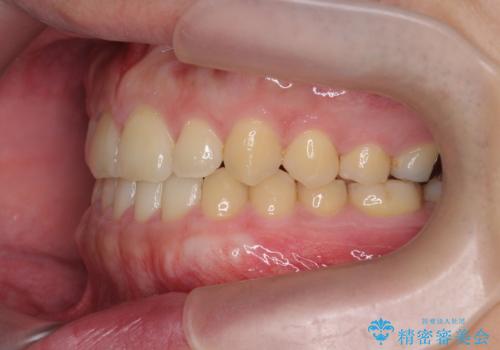

- 前歯の噛み合わせが反対になっていること、前歯の見た目の改善を希望され来院されました。

詳細な矯正検査の結果、顎の歪みが見られたため大きく歯を動かす治療ではなく前歯を主に並べることで前歯の前後関係を改善していきます。

前歯を主に動かす部分矯正であることからマウスピース矯正インビザラインによる治療を計画します。